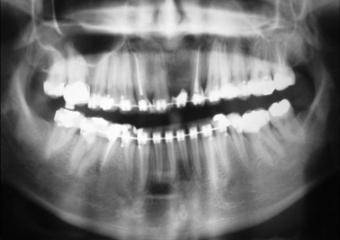

Imagens iniciais observando a ausência do incisivo central superior esquerdo

Raio X inicial